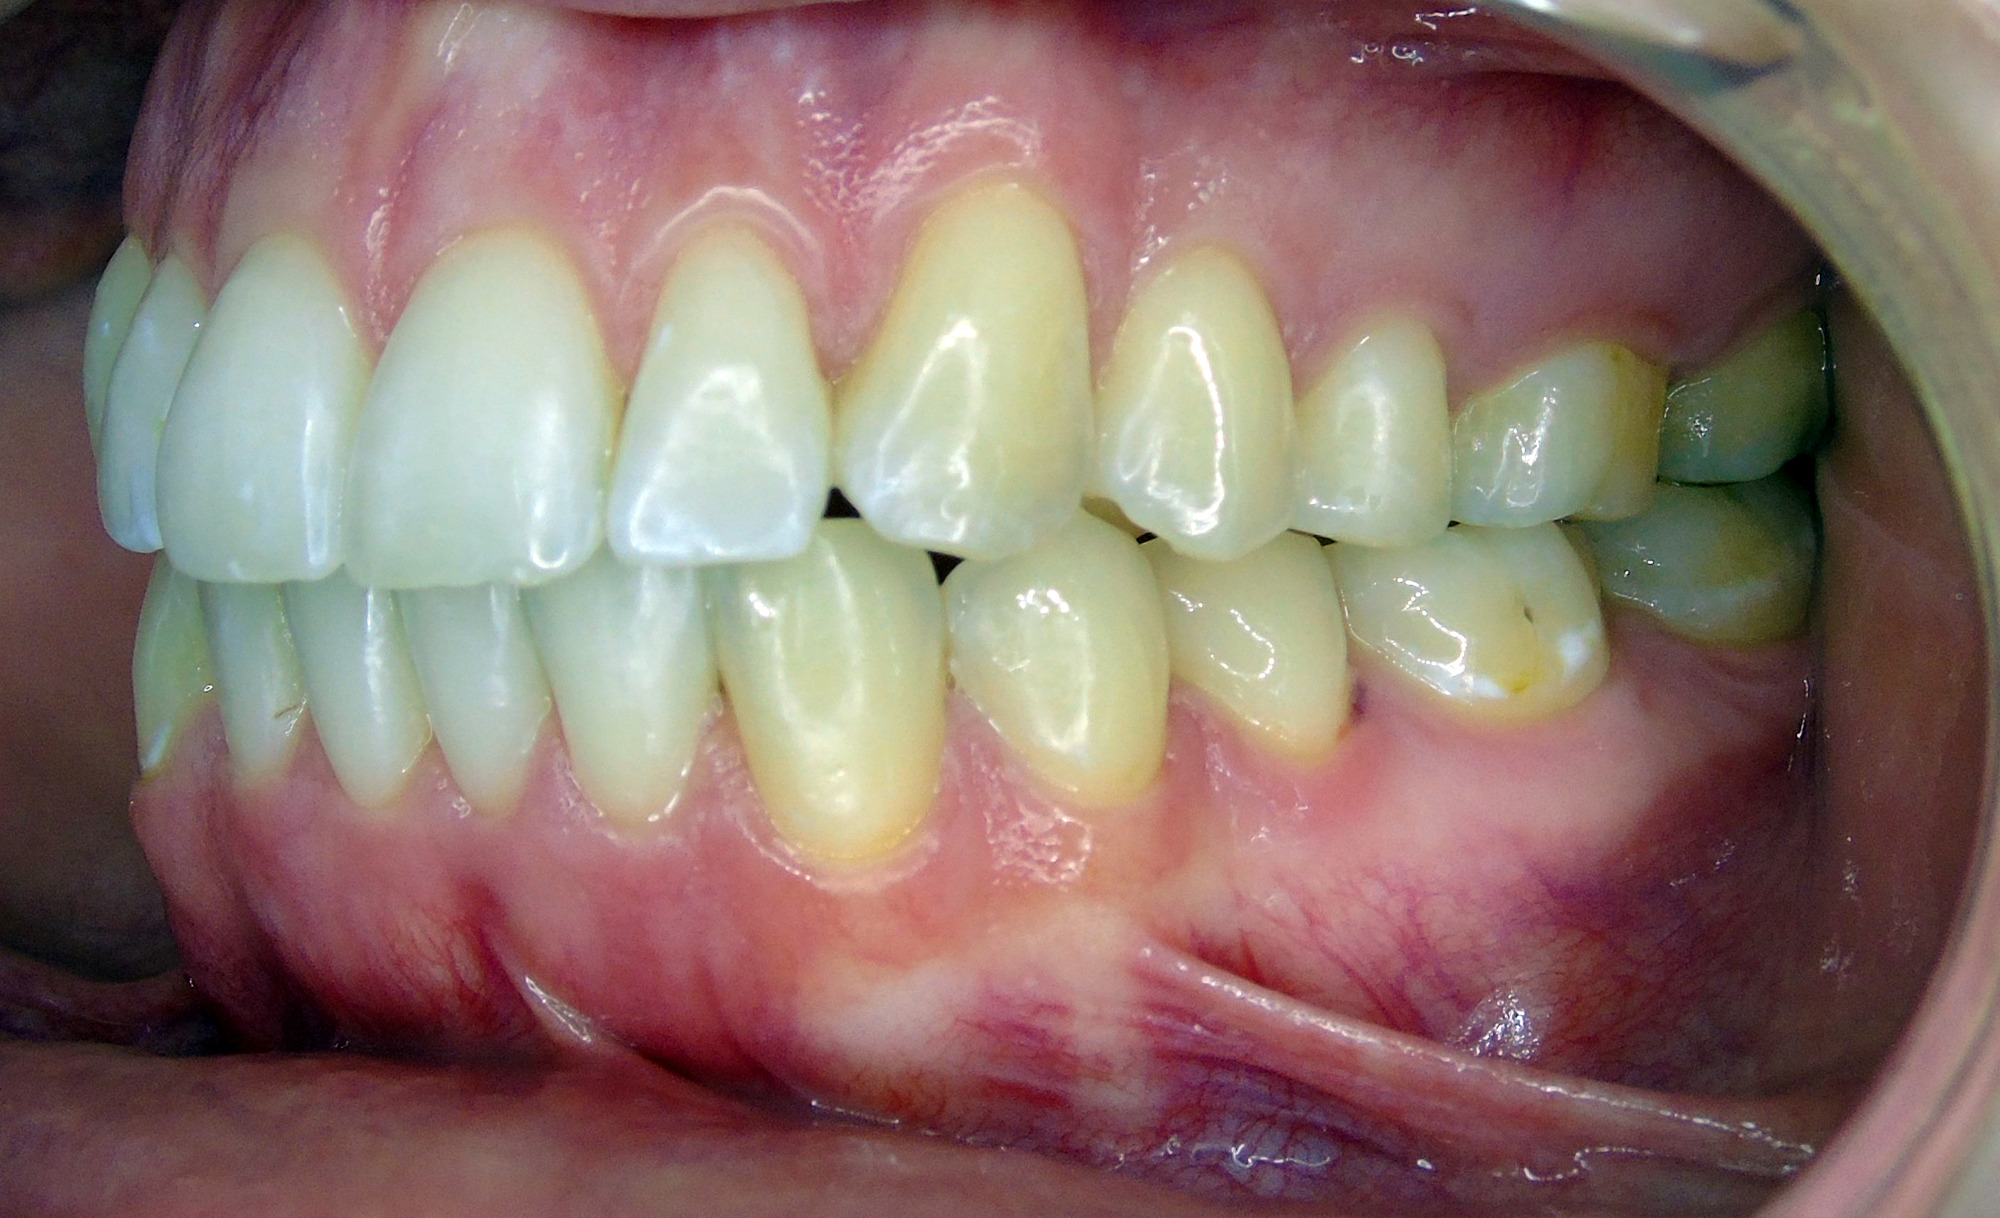

Intraoral evaluation disclosed an Angle class I on both sides, with an anterior open bite (-2.5mm), bialveolar protrusion and mild anterior crowding. Transversally, a narrow upper jaw has been observed. Furthermore, a persistent visceral swallowing pattern and misalignment of the midlines were found.

As can be seen in the images, the planned vertical correction was fully achieved. It has been noticed that Spark™ Clear Aligners have also helped with the patient’s visceral swallowing pattern, by shielding the tongue which then can no longer (unconsciously) rest between the teeth.